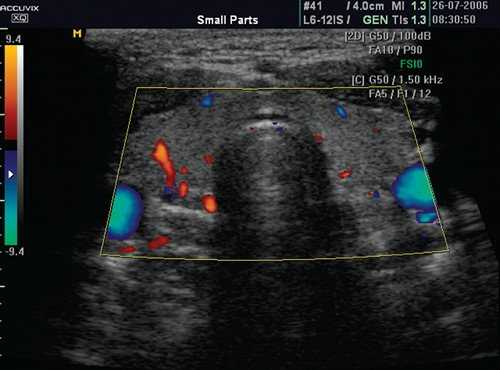

(Справа) Энергетическая допплерография, поперечная проекция: определяется диффузное повышение васкуляризации железы, часто описываемое как «тиреоидный пожар» при болезни Грейвса. При спектральной допплерографии (изображения не показаны) в сосудах обнаруживается повышение скорости кровотока в отличие от тиреоидита Хашимото (скорость не изменена). (Слева) КТ глазниц, корональная реформатированная проекция: определяется распространенная гипертрофия экстраокулярных мышц, сопоставимая с офтальмопатией Грейвса.

о Цветовая допплерография: выраженная диффузная гиперваскуляризация паренхимы, «тиреоидный пожар»

о Спектральная допплерография: повышение пиковой скорости кровотока (до 120 см/с) в нижней щитовидной артерии